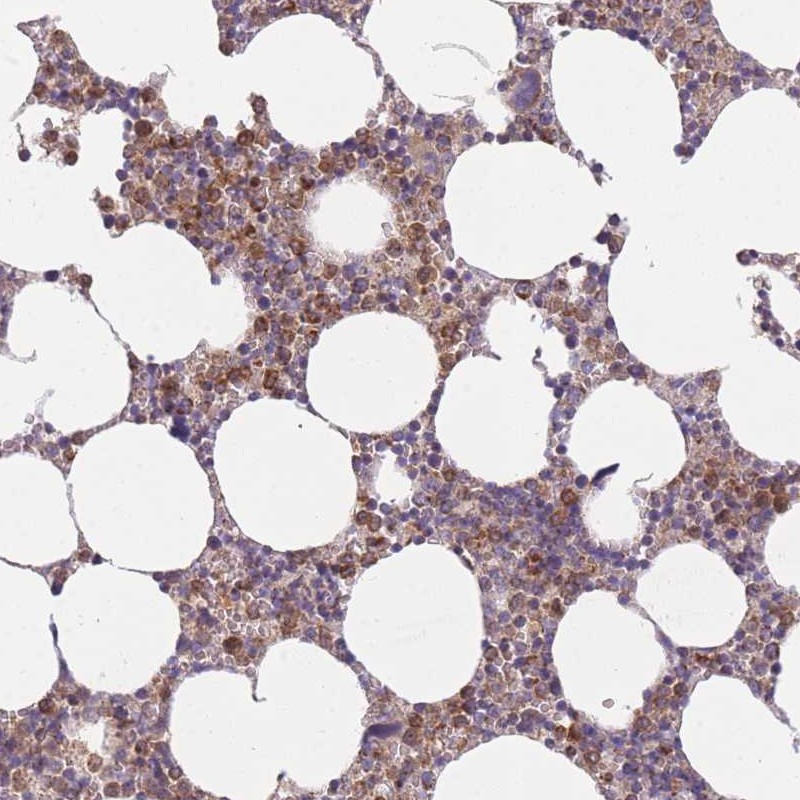

Immunohistochemical staining of human bone marrow shows moderate cytoplasmic positivity in hematopoietic cells.